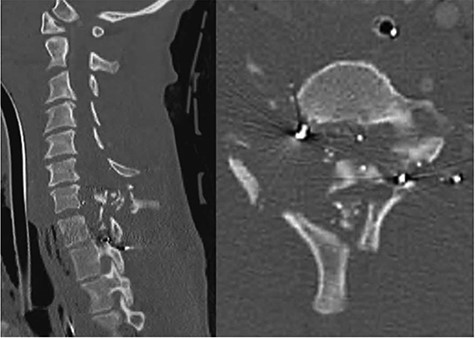

A 39-year-old African–American male presented with a gunshot wound through the right neck. The patient suffered a comminuted C6, C7 and T1 fractures with suspected right vertebral artery injury (Fig. 3). The patient was taken emergently to the operating room by the trauma surgery team for emergent neck exploration, right external jugular vein ligation and partial wound closure. The patient was noted to have a C4 ASIA A spinal cord injury. On hospital Day 2 the patient underwent a digital subtraction angiogram and embolization of a right vertebral arteriovenous fistula. On hospital Day 3, the patient was noted to have a CSF leak. Despite additional attempts to achieve a wound closure and several days of conservative management, the csf leak persisted. We decided to place an EVD because the spinal canal at c6/7 appeared completely obliterated.

CT cervical spine; sagittal (left): demonstrates comminuted c6, c7 and T1 fractures, and the axial (right) demonstrated complete spinal obliteration with bullet and bone fragments at the C6/7 level.